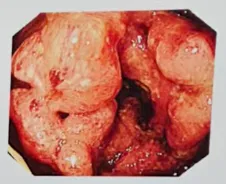

(图片来源于:央视网《生活圈》)

肠息肉:肠癌最常见的 “前身”

大肠癌大部分是由息肉发展来的息肉最开始是良性的。但是在摩擦、刺激下息肉内有部分细胞突变,变成了癌细胞。因为大肠在体内,息肉又藏在大肠内部所以早期大肠癌基本没有任何症状,等到出现症状往往都是中晚期。